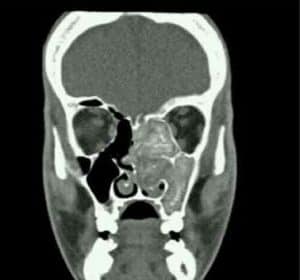

honey comb